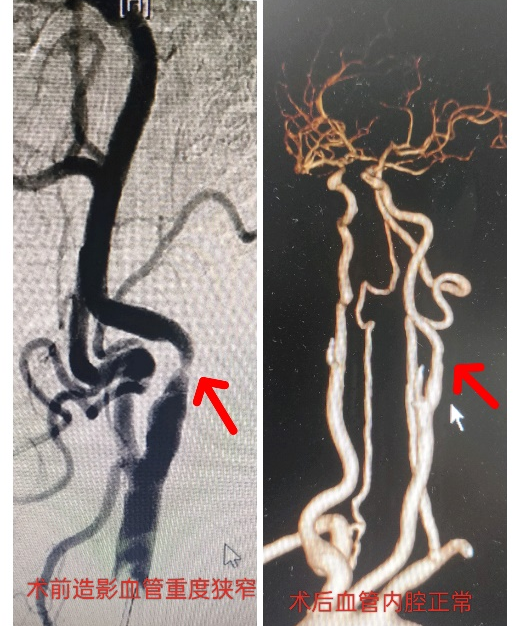

老孙因反复头晕、一过性脑缺血发作入院。经颈动脉超声及脑血管造影检查确诊为左侧颈动脉重度狭窄(狭窄率超过75%)。如不及时处理,引起血管狭窄的斑块随时可能脱落而导致大面积脑梗死,危及生命。

术前术后对比